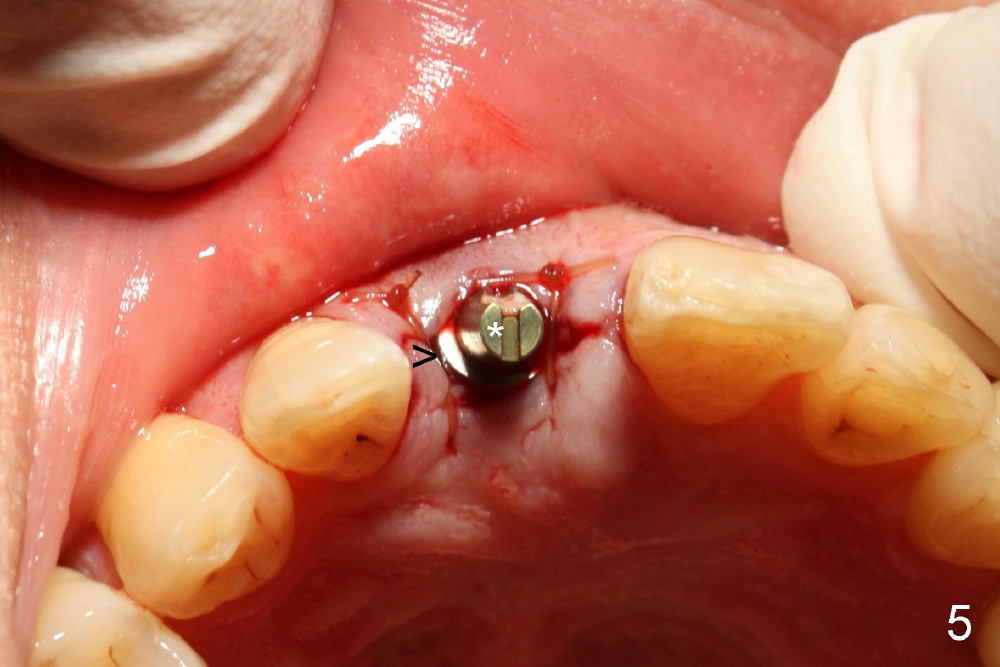

A 55-year-old man has severe pain on the upper right central incisor (Fig.1 *) after biting on a piece of bone. PA confirms crown fracture (Fig.2 <), extending subgingivally (Fig.3 >>). Osteotomy forms using a 2 mm pilot drill and 2.5-3.5 mm reamers (Fig.4). A 5x17 mm Tatum tapered implant is placed, autogenous bone placed in the buccal gap, sutures placed for wound approximation and 3.5 mm 20º angled abutment installed (Fig.5). An immediate provsional is fabricated (Fig.6), cemented and splinted (Fig.7).,